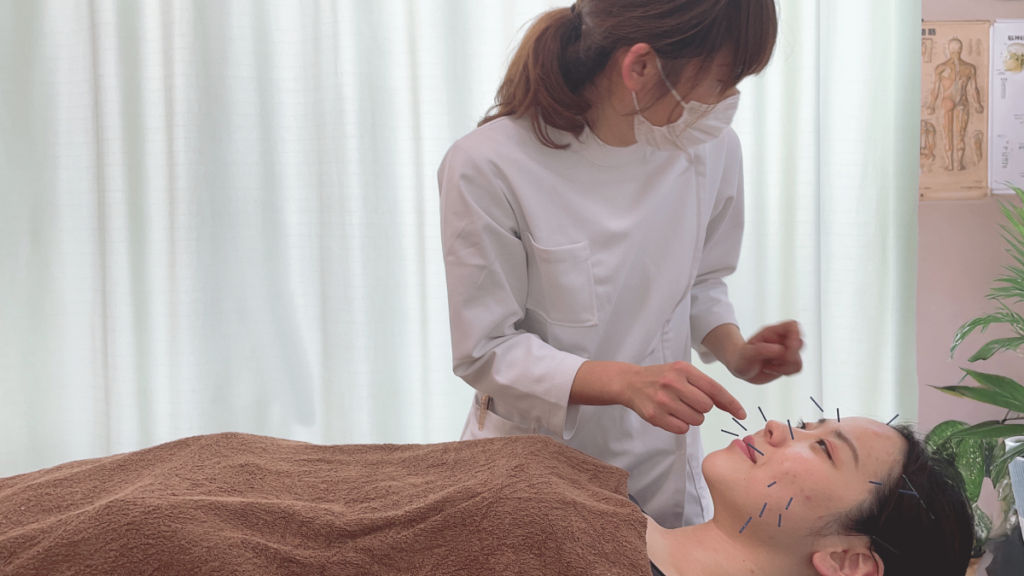

顔面部の皮膚や筋肉に鍼痛電を施すことにより、皮膚の再生(ターンオーバー)を推進することで、お肌の状態を改善します。全身の治療も行うことで、疲労の回復も行うことで、皮膚の代謝も改善します。